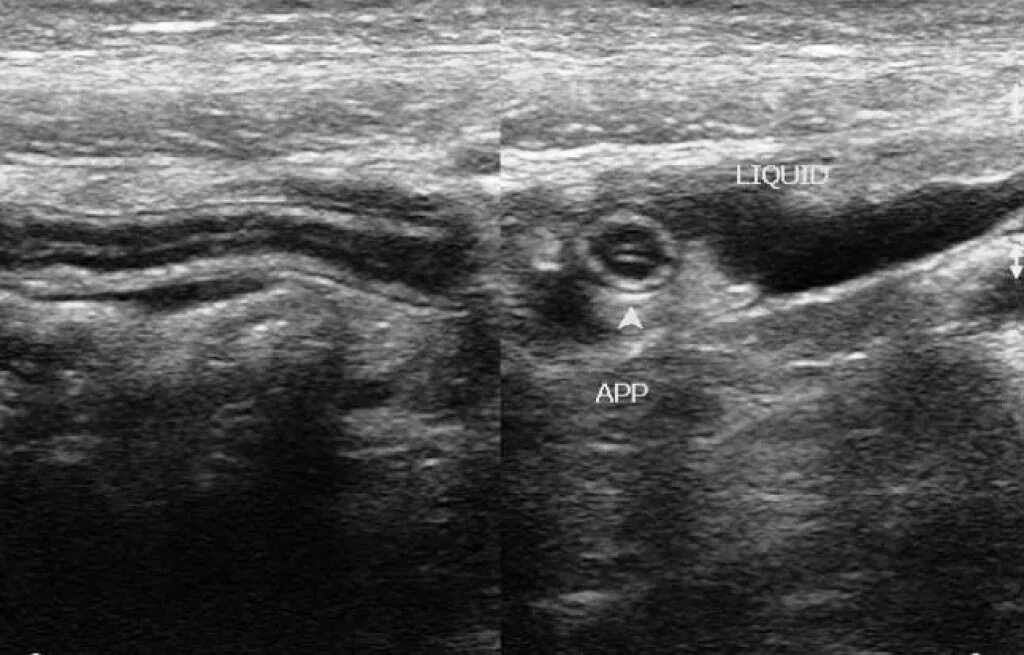

Какое узи при аппендиците